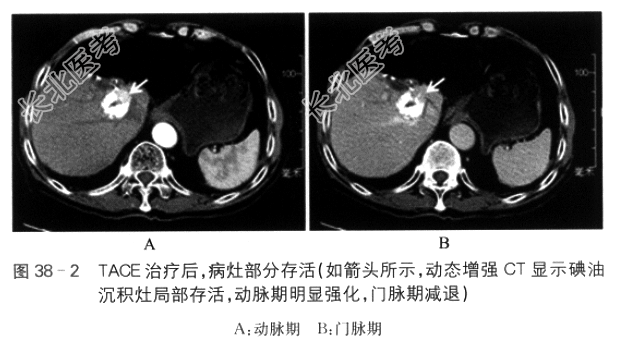

2010年8月患者体检发现AFP51.5ng/ml,当时无不适主诉,腹部CT诊断为肝癌,约10cm。2010年9月19日患者在我院行左半肝切除术,术后病理为肝细胞肝癌(HCC)。患者术后AFP下降至正常,此后每2个月门诊随访。2012年5月10日,彩超发现肝内1.8cm复发灶,AFP阴性;患者于2012年5月17日在我院行肝右叶部分切除术,术后病理为HCC。此后,继续每2个月门诊随访。2013年7月,彩超检查再次发现肝内约1.8cm复发灶,AFP阴性;患者在门诊接受6次无水酒精注射治疗。治疗1个月后,增强MRI提示肝内病灶坏死。2014年9月,患者彩超检查发现肝内约3.5cm复发灶,增强腹部CT确认肝内复发(见图38-1);AFP阴性。患者于2014年9月22日在我院行经导管动脉化学栓塞(TACE)治疗,术中肝动脉造影发现肝右叶一个约3.5cm肿瘤血管染色灶,经微导管超选至肝右动脉,给予表柔比星30mg与超液化碘油6ml制成混悬液栓塞,见病灶碘油沉积好。2014年11月3日在我院CT检查提示右叶病灶碘油沉积,局部存活(见图38-2)。此次为行肝癌射频消融治疗收治入院。整个病程中,患者无不适主诉,无黄疸、发热、腹胀、呕血、黑便,精神可,饮食、睡眠佳。

2014年11月3日腹部增强CT示肝癌介入治疗后改变,病灶部分存活。